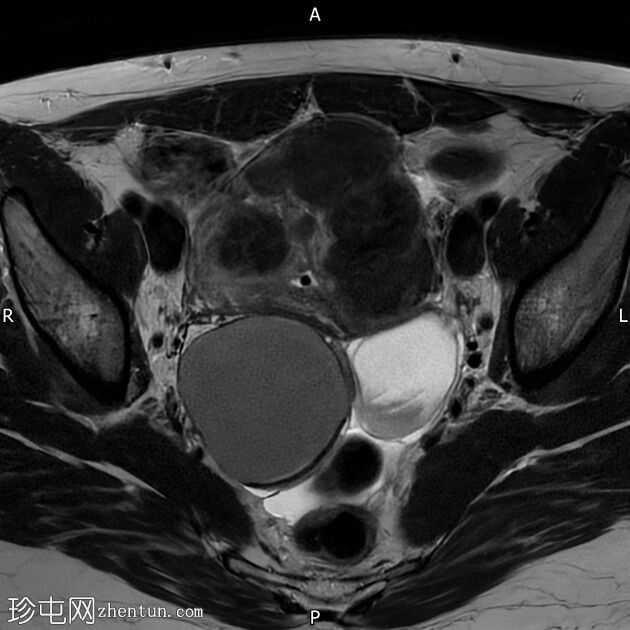

轴位

T2加权像

右侧卵巢囊肿,T2加权像呈低信号,T1脂肪抑制像呈高信号,大小为6 x 5.2 cm,符合子宫内膜异位囊肿的影像学表现。

左侧卵巢囊肿,T2加权像呈低信号,T1脂肪抑制像呈高信号,符合子宫内膜异位囊肿的影像学表现。

双侧卵巢粘连于后道格拉斯窝,呈“接吻卵巢征”。

多发性子宫肌瘤。宫内放置宫内节育器。

结论:双侧卵巢子宫内膜异位囊肿。多发性子宫肌瘤。

本病例显示右侧卵巢子宫内膜异位症,左侧卵巢囊肿内含出血性物质,并可见“接吻卵巢征”,诊断为卵巢子宫内膜异位囊肿伴可能粘连/深部盆腔子宫内膜异位症。